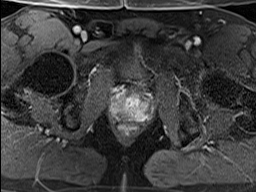

Tables 1 and 2 show our quantitative results: PSNR between the style (image we want to transfer style from) and generated image, SSIM and MS-SSIM between the content (image we want to take structure from) and generated image and finally, our proposed weighted SSIMs. For each style transfer direction and metric, our method consistently outperforms the other approaches. Figures 2 and 3 qualitatively highlight the good results of our method on 2D and 3D datasets. In addition, quantitative results on both figures show that our proposed metric preserves qualitative ordering of results for both style and content. In comparison, metrics such as SSIM struggle to accurately correlate to visual results.

Qualitative evaluation shows that the proposed method leads to sharper images, better content preservation, better localised CE and realistic MRI appearance. Quantitatively, we outperform the other algorithms with each metric, for each style transfer direction. While we expected that adding CE to images would be an easier task than removing CE, we found that for both tasks the method exhibits similarly performing quantitative and qualitative results. The results for style transfer with the kidney data show that when there is clear CE, it is easier to perform style transfer in both directions. However, when style transfer is performed on the prostate data, the model struggles in comparison to the kidney data. This may be due to the enhancement of the prostate being less defined than the kidney data. In figure 3(b), we can see the prostate with CE. Compared to figure 2(b) showing kidneys with CE, it is harder to determine the edges. The two original images shown in figures 3(a) and 3(b) are clear and easy to see some edges of prostate, in other images, it is harder to see the edges of the prostate.

(C) CW-SSIM: 0.94

(S) CW-SSIM: 0.75